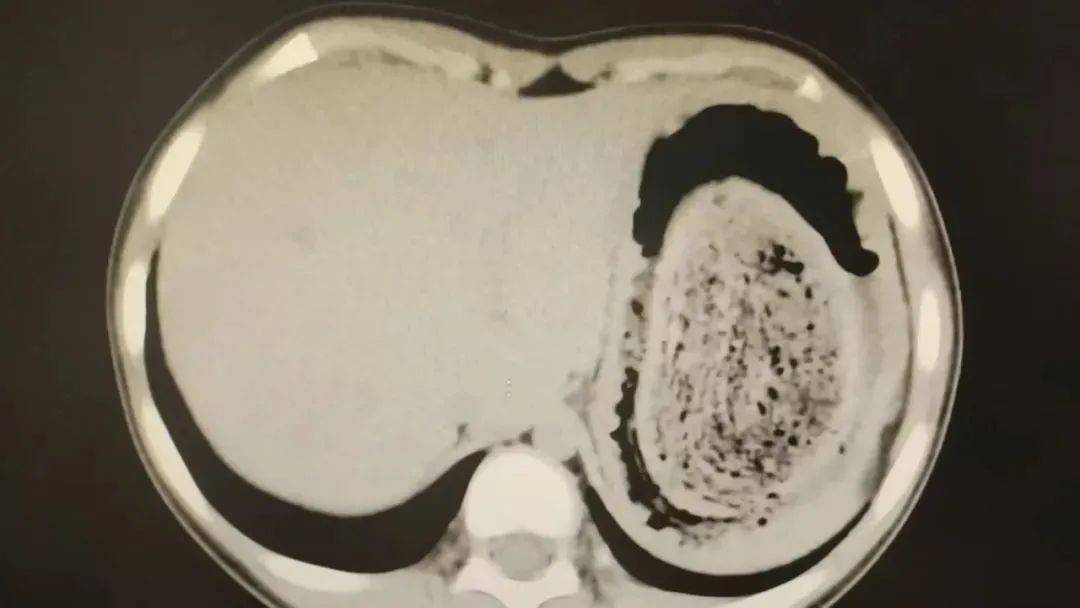

10岁女孩园园(化名)因持续3天的上腹痛伴呕吐被紧急送医皇冠登3管理出租 。影像学检查结果显示,她的胃部存在一个巨大的团块状阴影,初步怀疑为异物堵塞。据家长回忆,园园从1年前开始就有偷偷吃头发的习惯,但家人并未重视,直到这次症状严重才意识到问题的严重性。